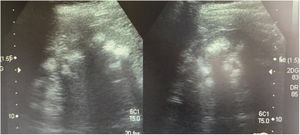

Case 3This was the 29-year-old mother of the patients, with a history of mother with diabetes and father with hypertension on treatment. She had an older brother with kidney stones and multiple episodes of flaccid paralysis. She was diagnosed after the investigations on her children. She had had a craving for water since childhood. She weighed 58 kg, was 157 cm tall and her blood pressure was 100/60 mmHg. Creatinine levels were 0.78 mg/dl (CrCl 122 ml/min), sodium 139 mEq/l, potassium 3.3 mEq/l and blood chloride 113 mEq/l. Venous blood gas analysis revealed metabolic acidosis (pH 7.17, HCO3− 14.1 mEq/l) with hypocitraturia (14 mg/24 h) and proteinuria 382 mg/24 h (Table 2). Her urinary pH was 7 and she had a positive urine anion gap (+36). Renal ultrasound revealed grade II-III medullary nephrocalcinosis (Fig. 3). A calculus was found in the lower segment of her right ureter and another 1.5 cm in size in her bladder. A genetic study was performed, analysing the genes ATP6V0A4, ATP6V1B1 and SLC4A1. A heterozygous pathogenic variant was found in exon 20 of the gene SLC4A1, c.2710_*12, p. (Tyr904_Val911delins68), resulting in a deletion of 39 bases (27 from the last exon and 12 from the 3′ UTR region), modifying the carboxy terminus of the protein (deletion of the last 8 amino acids and insertion of a new sequence of 68 amino acids). This variation, which is not described in the literature and not included in the database, is considered pathogenic, class 5 according to the American College of Medical Genetics and Genomics (ACMG) 2015 guidelines; the criteria used to classify it as class 5 are: PVS1, PM2, PM1 and PM4. This variation is not in the general population Genome Aggregation Database (gnomAD) (criterion PM2).

Ultrasound performed on the mother of the patients. Kidneys with heterogeneous echogenicity due to increased echogenicity of the renal pyramids consistent with grade II-III bilateral medullary nephrocalcinosis. Corticomedullary differentiation is poor, with signs of diffuse chronic nephropathy.